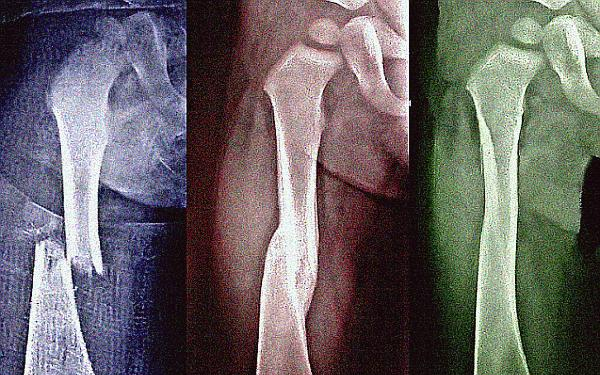

Gyógyuljon gyorsabban a törött csont

Sokan nem tudják, hogy a csonttörés után gyorsítani lehet a gyógyulást. Mindenekelőtt sok energiát vigyen be a szervezetébe, mert a csontok gyógyulásához energia kell.